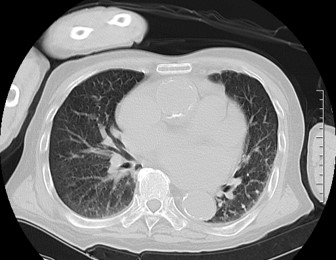

ハイピッチ使用時も 画質劣化が起きにくい

ハイピッチ使用時でも、画像を比較すると読影可能な画質を維持できている。図6の写真は左内腸骨動脈瘤の病変である。左側は患者が3か月に1回行っている定期フォロー時に撮影した通常ピッチ(0.984:1)の画像、右側は救急搬送時に撮影したハイピッチ(1.357:1)の画像であるが読影に影響が出る程の画質の差は感じられない。

Maxima_hachiojisanno10.jpg

図6 ピッチの違いによる左内腸骨動脈瘤の見え方の違い